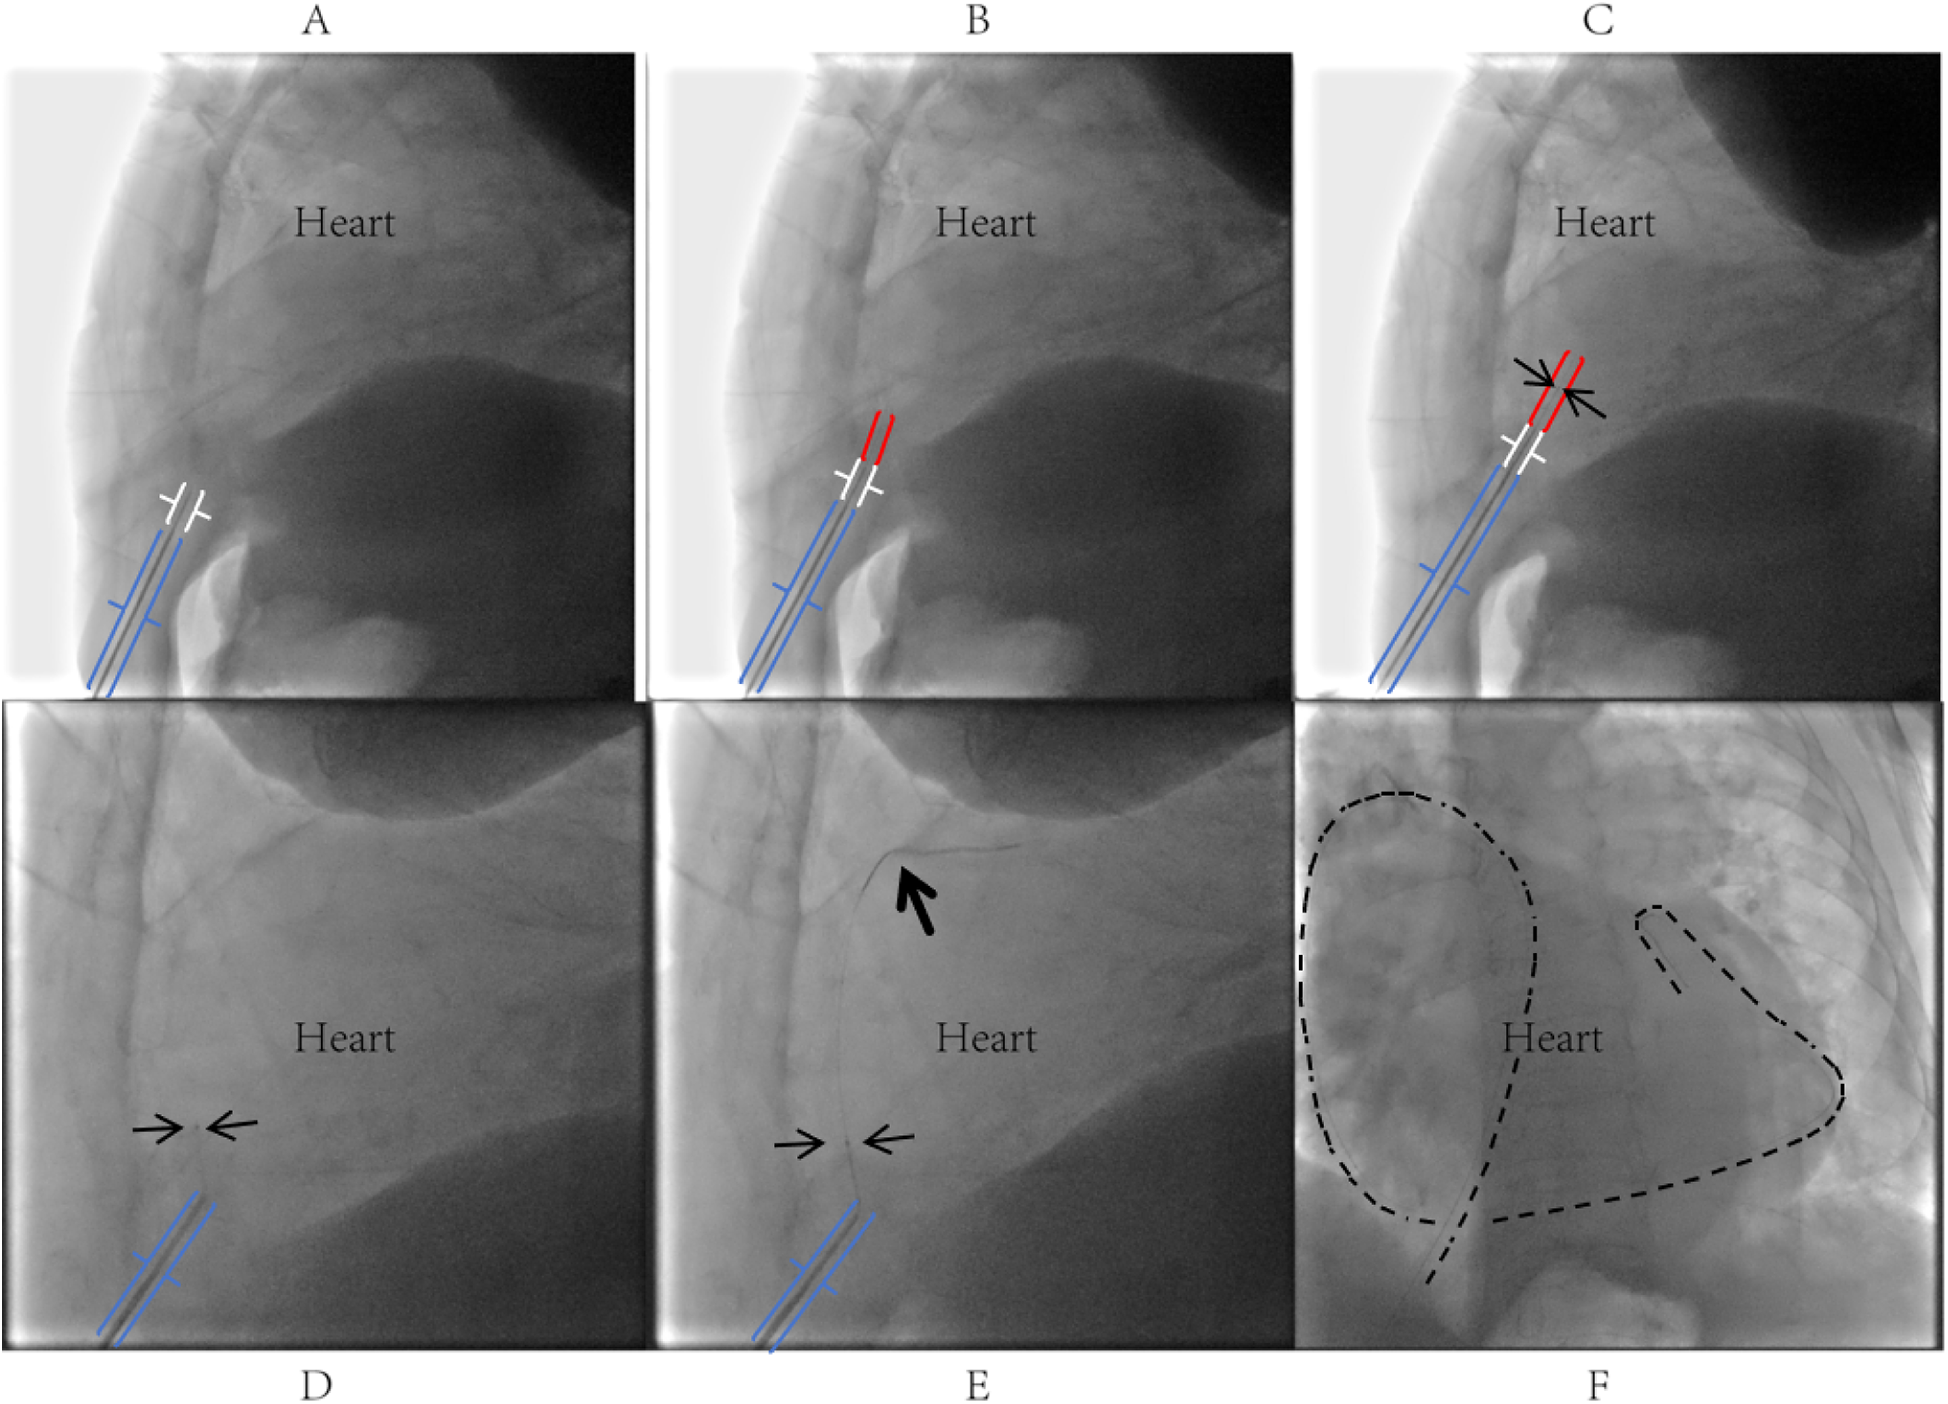

Figure 2

Procedural steps of PTCA guidewire-based pericardiocentesis. (A) Under left lateral fluoroscopic guidance, the puncture needle tip was inserted through the skin at the left costophrenic angle, traversed superficial tissues into the inferior region of Larrey's triangle (formed by the xiphoid process, right ventricle, and diaphragm), maintaining a 2–3 cm distance between the needle tip and cardiac silhouette; a blunt-tipped metal tube was slowly advanced through the needle lumen to approximate the parietal pericardium; (B) the stiff end of the PTCA guidewire was slowly advanced through the metal tube (MAP802 PhD Hemostasis valve, Merit Medical Systems, Inc.) to penetrate the parietal pericardium into the pericardial cavity; upon entering the pericardial cavity for approximately 1–2 cm, the guidewire typically exhibited subtle oscillations synchronized with cardiac pulsation; (C) a 1.8Fr Terumo Finecross microcatheter was advanced along the PTCA guidewire into the pericardial cavity and secured in place; (D) after withdrawing the guidewire, the soft end was reintroduced into the Terumo microcatheter and gently advanced into the pericardial cavity; (E,F) successful pericardial puncture was confirmed by observing the guidewire coiling along the cardiac contour, followed by insertion of a sheath or drainage catheter over the guidewire and microcatheter as clinically required.

Given the loculated nature of the effusion with pericardial adhesions, conventional pericardiocentesis was technically challenging, while the prolonged use of low-molecular-weight heparin for lower-limb thrombosis and atrial fibrillation further increased procedural risks. Therefore, digital subtraction angiography (DSA)-guided PTCA guidewire-based pericardiocentesis was performed using a Sion guidewire and Terumo microcatheter (Figure 2). Despite aspirating 350 ml of viscous purulent fluid, the drainage catheter became nonfunctional within three days, with worsening symptoms and unchanged effusion on TTE. Reintervention involved repositioning the catheter under DSA and advancing a J-tip guidewire through the existing tract. A 6F sheath was subsequently inserted, allowing aspiration of 400 ml of purulent fluid via the side port. The sheath was then exchanged for a central venous catheter, through which 5 mg of alteplase (diluted in 20 ml of saline) was instilled into the pericardium. The catheter was clamped for 24 h to facilitate fibrinolysis, yielding an additional 400 ml of drainage over 72 h (Figure 3).

To address this, we employed a novel approach using a blunt-tipped, highly flexible PTCA guidewire (Sion). Under DSA guidance, the puncture needle was advanced to a position 2–3 cm from the pericardium, after which the blunt-tipped metal tube (MAP802 PhD Hemostasis valve, Merit Medical Systems, Inc.) was inserted until its tip contacted the fibrous pericardium. The guidewire's distal end was then used to penetrate the fibrous pericardial layers. with the support of the blunt- tipped metal tube. Then the soft end of the guidewire exchanged into the pericardium space with a 1.8Fr microcatheter. The absence of rigid needle support and reduced forward resistance allowed controlled entry into the pericardial space, significantly lowering the risks of myocardial laceration and iatrogenic tamponade compared to traditional techniques. Post-procedural intrapericardial instillation of 5 mg of alteplase (diluted in 20 ml saline) with 24-h catheter clamping achieved effective drainage (400 ml over 72 h) without complications such as hemorrhage or allergic reactions. Combined with targeted antibiotics, this approach led to complete recovery without sequelae.